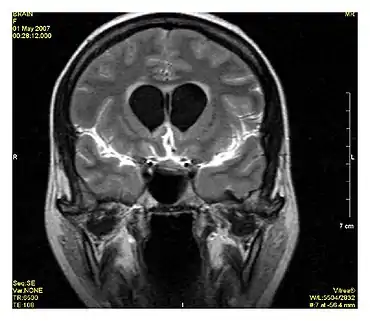

Neuroimaging

MRI is the investigative tool of choice for neurological cancers over CT, as it offers better visualization of the posterior cranial fossa, containing the brainstem and the cerebellum. The contrast provided between grey and white matter makes MRI the best choice for many conditions of the central nervous system, including demyelinating diseases, dementia, cerebrovascular disease, infectious diseases, Alzheimer's disease and epilepsy.[22][23][24] Since many images are taken milliseconds apart, it shows how the brain responds to different stimuli, enabling researchers to study both the functional and structural brain abnormalities in psychological disorders.[25] MRI also is used in guided stereotactic surgery and radiosurgery for treatment of intracranial tumors, arteriovenous malformations, and other surgically treatable conditions using a device known as the N-localizer.[26][27][28] New Artificial intelligence in healthcare tools have demonstrated higher image quality and morphometric analysis in neuroimaging with the application of a denoising system.[29]